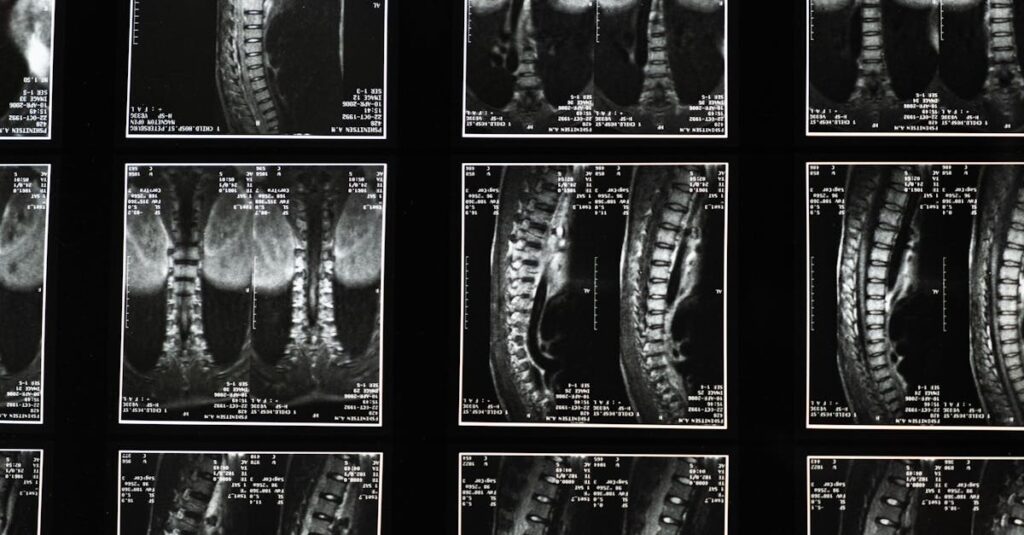

La sciatique se manifeste par des douleurs le long du nerf sciatique, qui s’étend du bas du dos jusqu’aux jambes. Elle est souvent due à la compression du nerf, causée par des problèmes tels qu’une hernie discale, une sténose spinale ou des tensions musculaires. Cette douleur peut se traduire par des sensations d’engourdissement, de picotement et parfois une faiblesse musculaire.